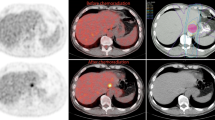

None of the 112 patients had foci of increased FDG uptake visible in the liver on baseline PET/CT. New foci of increased hepatic FDG avidity were seen in 10 of the 112 patients (9%) on the post-treatment PET/CT examinations, 6 (6%) of which had corresponding regions of faint hypoattenuation on the corresponding non-contrast CT. Benignity of the FDG-avid foci was confirmed in 9 (8%) of patients with 1 (1%) patient determined to have metastatic disease (Table 1). The mean SUVmax of the FDG-avid foci determined to be radiation-induced liver was 5.7 (range 5.0–8.8). A representative case is illustrated in Figure 1. The patient with confirmed hepatic metastasis (Fig. 2) exhibited a lesion SUVmax of 12.8.

A Axial PET image in a 63-year-old man 5 weeks after completion of neoadjuvant chemoradiation for distal esophageal cancer shows a focus of increased FDG avidity (arrow; SUVmax 6.0) in the caudate lobe. B Corresponding axial contrast-enhanced CT image demonstrates a subtle focus (arrow) of reduced enhancement with straight margins. This abnormality resolved on subsequent contrast-enhanced CT (not shown), and the final diagnosis was radiation-induced liver disease.

Common sites of metastatic spread in esophageal cancer include the abdominal lymph nodes, liver, and lungs [10, 23–26]. In one study, it was shown that up to 35 % of patients with esophageal cancer will develop liver metastases [29]. In addition to metastatic disease, the liver is also particularly prone to radiation-induced liver disease during radiotherapy of distal esophageal cancer, due to the close proximity of the left lobe which is accordingly included in the standard radiation field [27–29]. Given that serial PET/CT is increasingly performed during neoadjuvant chemoradiation of esophageal cancer and that both metastases and radiation-induced liver disease may manifest as increased foci of FDG avidity at PET scanning, our study provides important results that address how these two entities might be distinguished. First, we found that new foci of hepatic FDG avidity developing during neoadjuvant chemoradiation of esophageal cancer are usually due to radiation-induced liver disease. Increased FDG avidity in radiation-induced liver disease results from inflammation caused by radiation with increased FDG uptake by active leukocytes [30]. This simple observational result is statistically reassuring, and likely reflects the low likelihood of metastases developing during neoadjuvant chemoradiation. Second, while based on small numbers, we found that the location of the new foci of FDG avidity may be important. All the foci due to radiation-induced liver disease developed in the left and caudate lobes (Fig. 1), within the presumed radiation field, while the sole case of metastatic disease developed in the inferior right hepatic lobe, remote from the primary tumor and radiation field (Fig. 2).